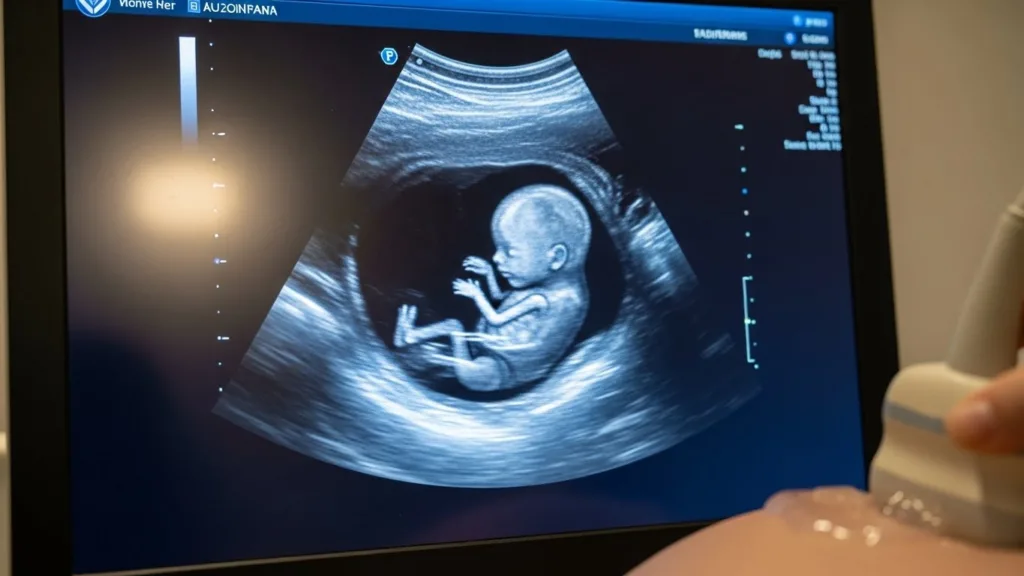

At Our Baby Hospital, we provide high-quality ultrasound services to support accurate diagnosis, pregnancy monitoring, and women’s health care. Our imaging services are designed to deliver clear results, timely answers, and reassurance for patients at every stage of care.

Our ultrasound examinations are performed by trained professionals using modern equipment to capture detailed images that support accurate medical decisions.

We use up-to-date ultrasound systems for obstetric, gynecologic, and general diagnostic imaging, ensuring reliable results without radiation exposure.

Ultrasound is a safe, non-invasive imaging method that uses sound waves to create real-time images of internal organs, tissues, and developing babies during pregnancy.